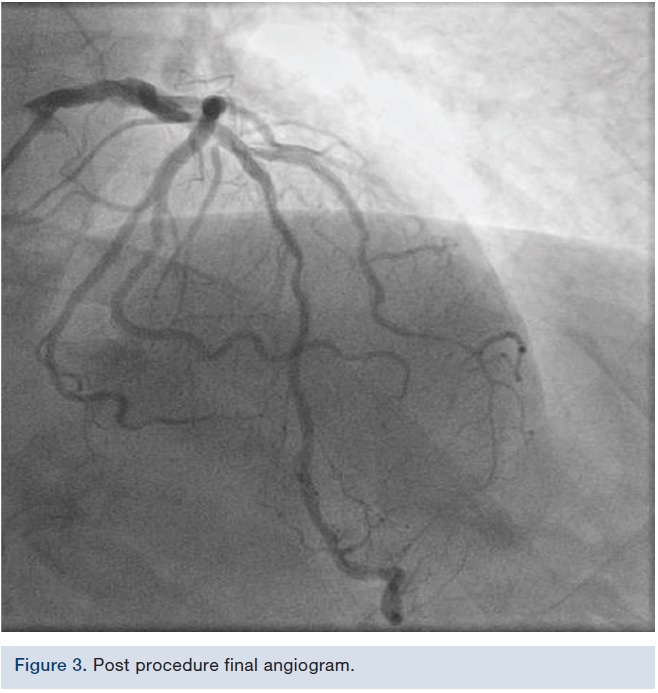

We used a 6 French Extra Backup (EBU) 3.5 guide (Medtronic). We initially put a Runthrough wire (Terumo) down the diagonal and a Samurai wire (Boston Scientific) down the LAD. We then took a 0.9 laser after bivalirudin was administered and tried to cross into the diagonal; however, there was wire bias. The wire was pulled from the LAD into the diagonal, the laser was placed across the ostium, and then we rewired the LAD. Laser atherectomy was performed at a setting of 60/40, debulking the in-stent restenosis. We were then able to deliver a 2.5 x 10 mm AngioSculpt (Spectranetics), predilated, and placed a 2.5 x 24 mm Synergy drug-eluting stent (Boston Scientific) at 12 atmospheres. We post dilated with a 2.75 NC balloon (Medtronic), staying short of the ostium, because there was concern about where the stent was located. However, once we post dilated the stent, TIMI-3 flow was visible in both vessels. There was disease beyond the stent that was possibly wire spasm, but plaque shift in the LAD was visible as well, and on magnified views, it appeared that the struts might have been hanging out in the LAD, which would be why, when we manipulated the devices into the diagonal, some plaque shift took place in the LAD. There now appeared to be a 90% stenosis in the LAD focal right afterwards. Nitroglycerin was given and it did not resolve; therefore, we elected to go ahead and fix it. A Runthrough wire was put down the LAD and then a 2.75 x 12 mm noncompliant balloon that was used in the diagonal was dilated in the LAD. We crushed the ostium with the diagonal stent, and were then able to deliver a 3.0 x 16 mm stent going across the diagonal and overlapping with the previous LAD stent. The stent was deployed at 14 atmospheres. The LAD was rewired with the Runthrough wire and the Samurai wire pulled back. The diagonal was wired with the Samurai wire and now both wires were crossed. A 2.0 mm compliant balloon in the diagonal was dilated to 14 atmospheres, opening up the struts. A 3.0 x 12 mm noncompliant balloon was placed in the LAD and a 2.5 x 15 mm compliant balloon was placed in the diagonal. Nominal inflations were performed in both vessels, in a kissing manner. Final angiography revealed TIMI-3 flow without dissection, perforation, or embolization. The wires were removed. Orthogonal views were obtained, revealing TIMI-3 flow without dissection, perforation, or embolization. The patient tolerated the procedure well. The guide was removed and a TR Band (Terumo) was placed over the radial artery.Discussion